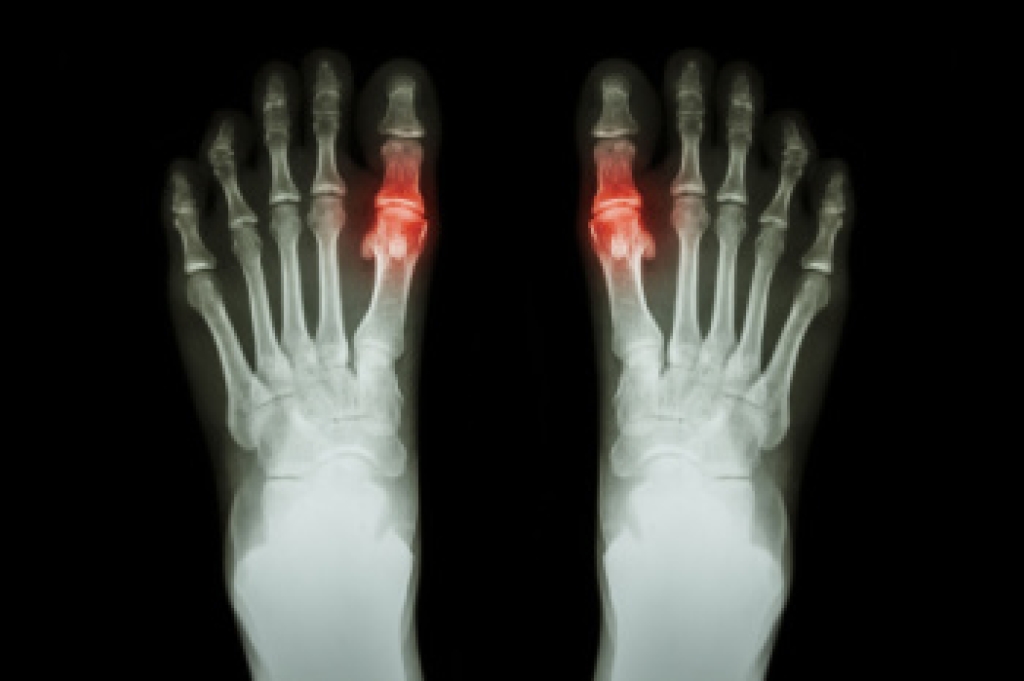

In every workplace, the risk of falling is a significant concern that demands attention. Mitigating this risk requires a proactive approach and a commitment to safety from both employers and employees alike. First and foremost, maintaining a clean and clutter-free environment is important, as objects left in walkways can easily become tripping hazards. Furthermore, ensuring that floors are dry and free from spills helps prevent slips. Adequate lighting also plays a vital role in enhancing visibility and reducing the likelihood of accidents. Implementing proper training programs for employees is indispensable. This includes educating workers on the importance of using appropriate safety equipment such as non-slip footwear and harnesses when working at heights. Additionally, promoting a culture of mindfulness where employees are encouraged to report potential hazards and participate in safety inspections fosters a safer work environment for everyone. The feet are often hurt when falling occurs, which may compromise the ability to perform daily tasks. If you are interested in having additional knowledge about how falling can impact the feet and methods to prevent this, it is suggested that you consult a podiatrist who can provide you with the information you are seeking.